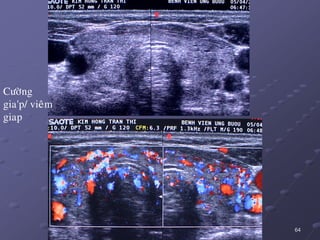

 SA: TG cöùng khoâng to hay to ít, echo keùm lan toaû, coù theå coù

caùc haït echo daày treân neàn giaùp echo keùm  duøng SA maøu ñeå

phaân bieät vôùi. ÔÛ theå tieán trieån, khoâng coøn thaáy ñöôïc caáu truùc

echo bình thöôøng cuûa TG, maø ñöôïc thay theá baèng moâ echo raát

keùm hay echo raát daày vaø haáp thu soùng aâm maïnh.

 Taêng nguy cô ung thö giaùp daïng nhuù vaø lymphoâm/ Vieâm coù suy

giaùp: FNAC khi taêng nhanh theå tích TG.

64

Cöôøng

gia'p/ vieâm

giap